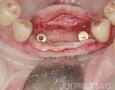

Surgery